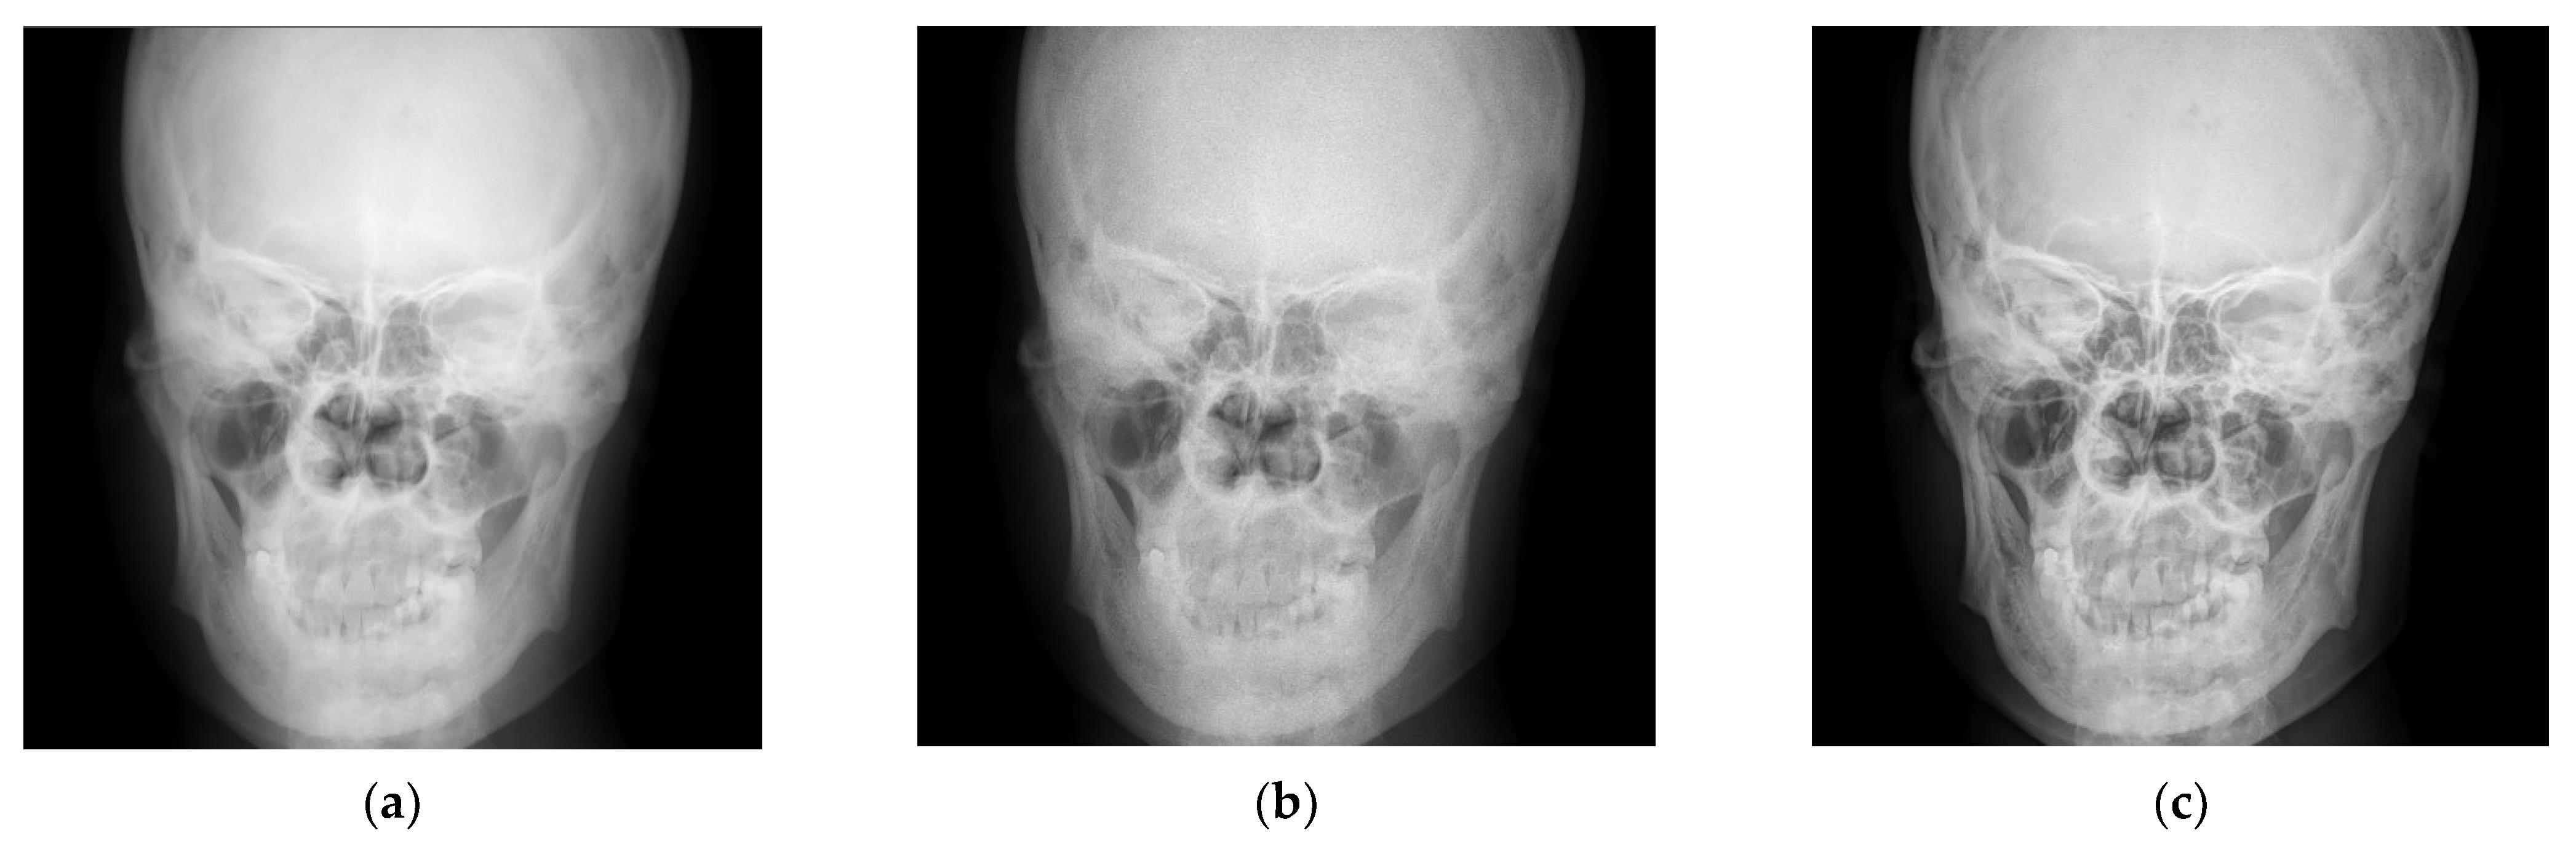

4.1. Simulations for Multicale Diagnostic Detail Enhancement on DR Images